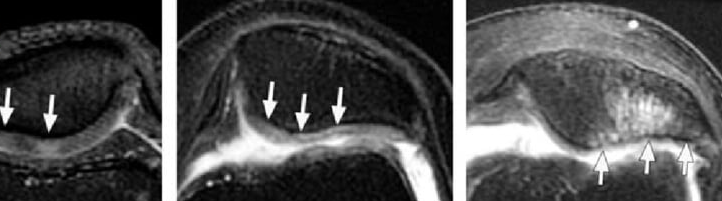

Qual é o principal achado na RNM da condromalácea patelar?

Edema ósseo e lesões na cartilagem patelar.